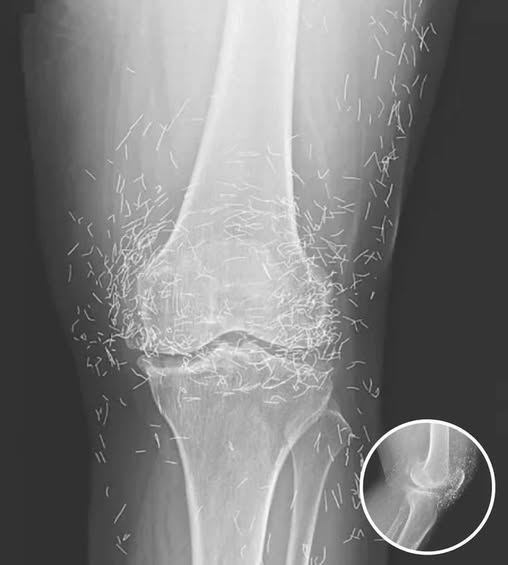

A routine X-ray revealed an unexpected surprise when doctors examined the knees of a 65-year-old woman suffering from severe joint pain. What they found was nothing short of astonishing — hundreds of tiny gold needles embedded deep in her tissue.

The woman, from South Korea, had been battling osteoarthritis for years. The painful condition breaks down cartilage and bone inside the joints, leading to stiffness and swelling. When standard treatments such as painkillers and anti-inflammatory medications failed to provide relief — and instead caused stomach problems — she turned to a popular alternative: acupuncture.

Acupuncture, a traditional therapy widely used in Asia, involves inserting thin needles into specific points on the body in an effort to relieve pain or treat illness. In this case, however, doctors say the gold needles were left behind intentionally as part of her treatment plan, designed to deliver continuous stimulation to the affected area.

There are other complications as well. Needles lodged in tissue can interfere with medical imaging. “They can obscure parts of the anatomy on an X-ray,” Guermazi noted. Even more alarming, patients with metal fragments in their bodies should never undergo an MRI, as the magnetic force could cause the needles to move — potentially puncturing blood vessels and causing life-threatening damage.

As for the South Korean woman, her case was recently documented in the New England Journal of Medicine. While the needles may have been intended to help, her X-rays tell a cautionary tale about the potential risks of extreme alternative therapies.